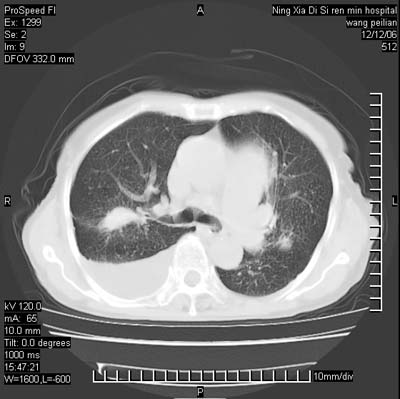

标题: CT5609:胸部:女77 病史不详 [打印本页]

标题: CT5609:胸部:女77 病史不详

两肺可见多个大小不等的结节,左侧有胸水,纵隔淋巴结增大,考虑是细支气管肺泡癌

两肺尖纤维索状影,两下肺结节块状影,且有钙化灶,右胸腔积液。考虑肺结核并胸膜炎。

双侧肺结核伴右侧胸腔积液.

两肺尖纤维索状影,两下肺结节块状影,且有钙化灶,右胸腔积液。考虑肺结核并胸膜炎肺间质纤维化

考虑:1、慢性支气管炎合并全小叶型肺气肿、间质纤维化;

2、双肺结核;

3、右侧胸膜炎(积液)。

1、双肺继发型肺结核(以纤维、增殖灶为主);

2、右侧胸腔积液;

3、其余符合老年肺改变。

双肺见多个结节状及条索状影,双侧胸腔积液,右侧叶间积液,考虑结核性胸膜炎